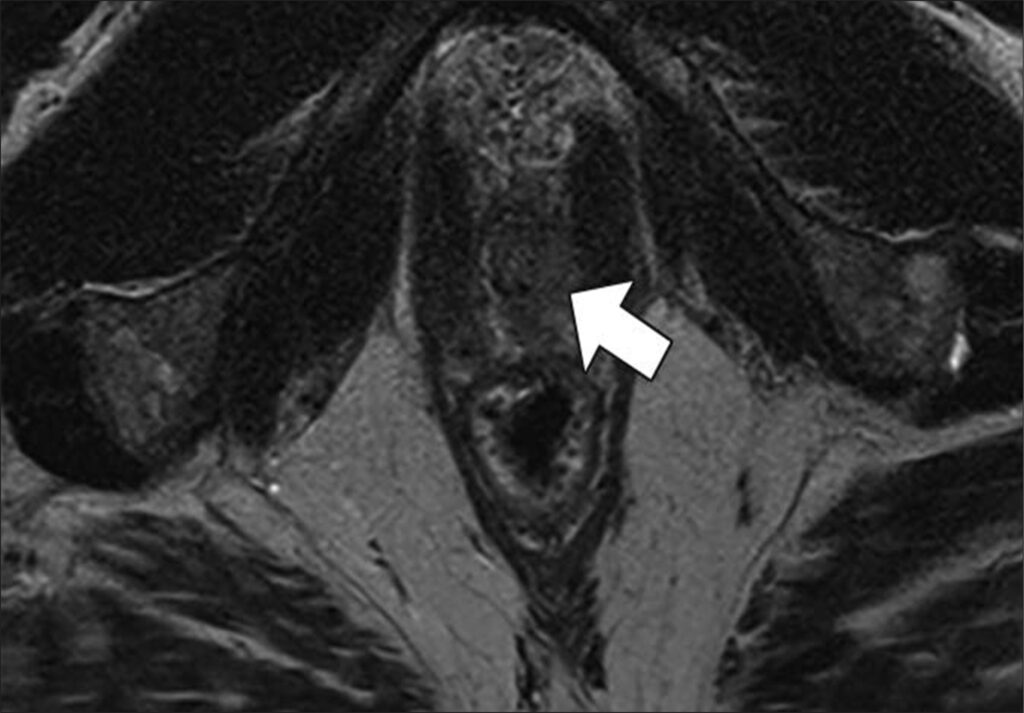

47-year-old man with history of two negative systematic biopsies at another facility and increasing PSA level (most recently, 35.6 ng/mL). Multiparametric MRI was performed for persistent clinical suspicion of clinically significant prostate cancer

Top to Bottom: Axial T2-weighted (Top), axial high-b-value (2000 s/mm2) (Middle), and calculated ADC (Bottom) MR images show left apical anterior central gland lesion (arrow) with very high suspicion of being clinically significant prostate cancer. Lesion is PI-RADS category 5. MRI–transrectal ultrasound fusion biopsy of lesion resulted in pathologic diagnosis of prostatic adenocarcinoma, Gleason 4 + 3 = 7 (grade group 3). Gleason 4 pattern represents 60% of tumor. Prostate volume calculated with MRI is 40 mL.